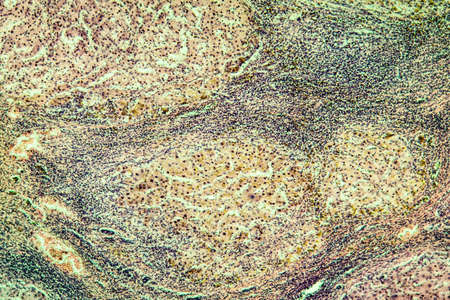

Biological histological fixed colored preparation of the spleen - a secondary organ of the immune system